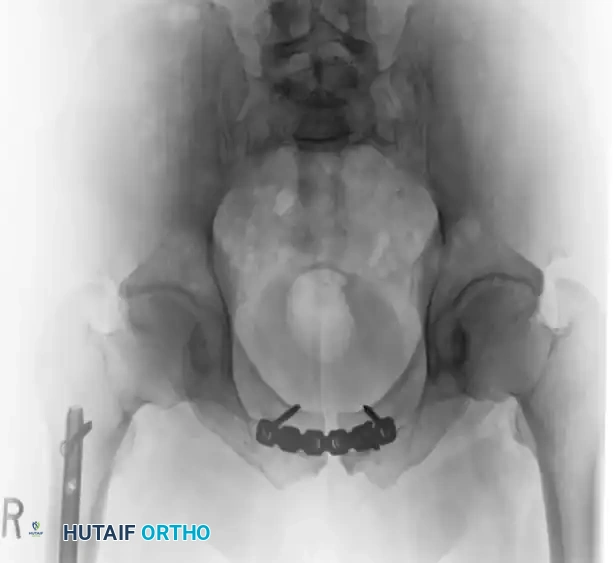

Postoperative Imaging:

Postoperative AP, inlet, and outlet views confirm anatomic reduction of the anterior ring and restoration of pelvic volume.

FIGURE 56-43: Young and Burgess anteroposterior type II (AP II) pelvic ring injury with pubic diastasis treated with anterior fixation. A and B, Preoperative views. C-E, Postoperative anteroposterior, inlet, and outlet views.